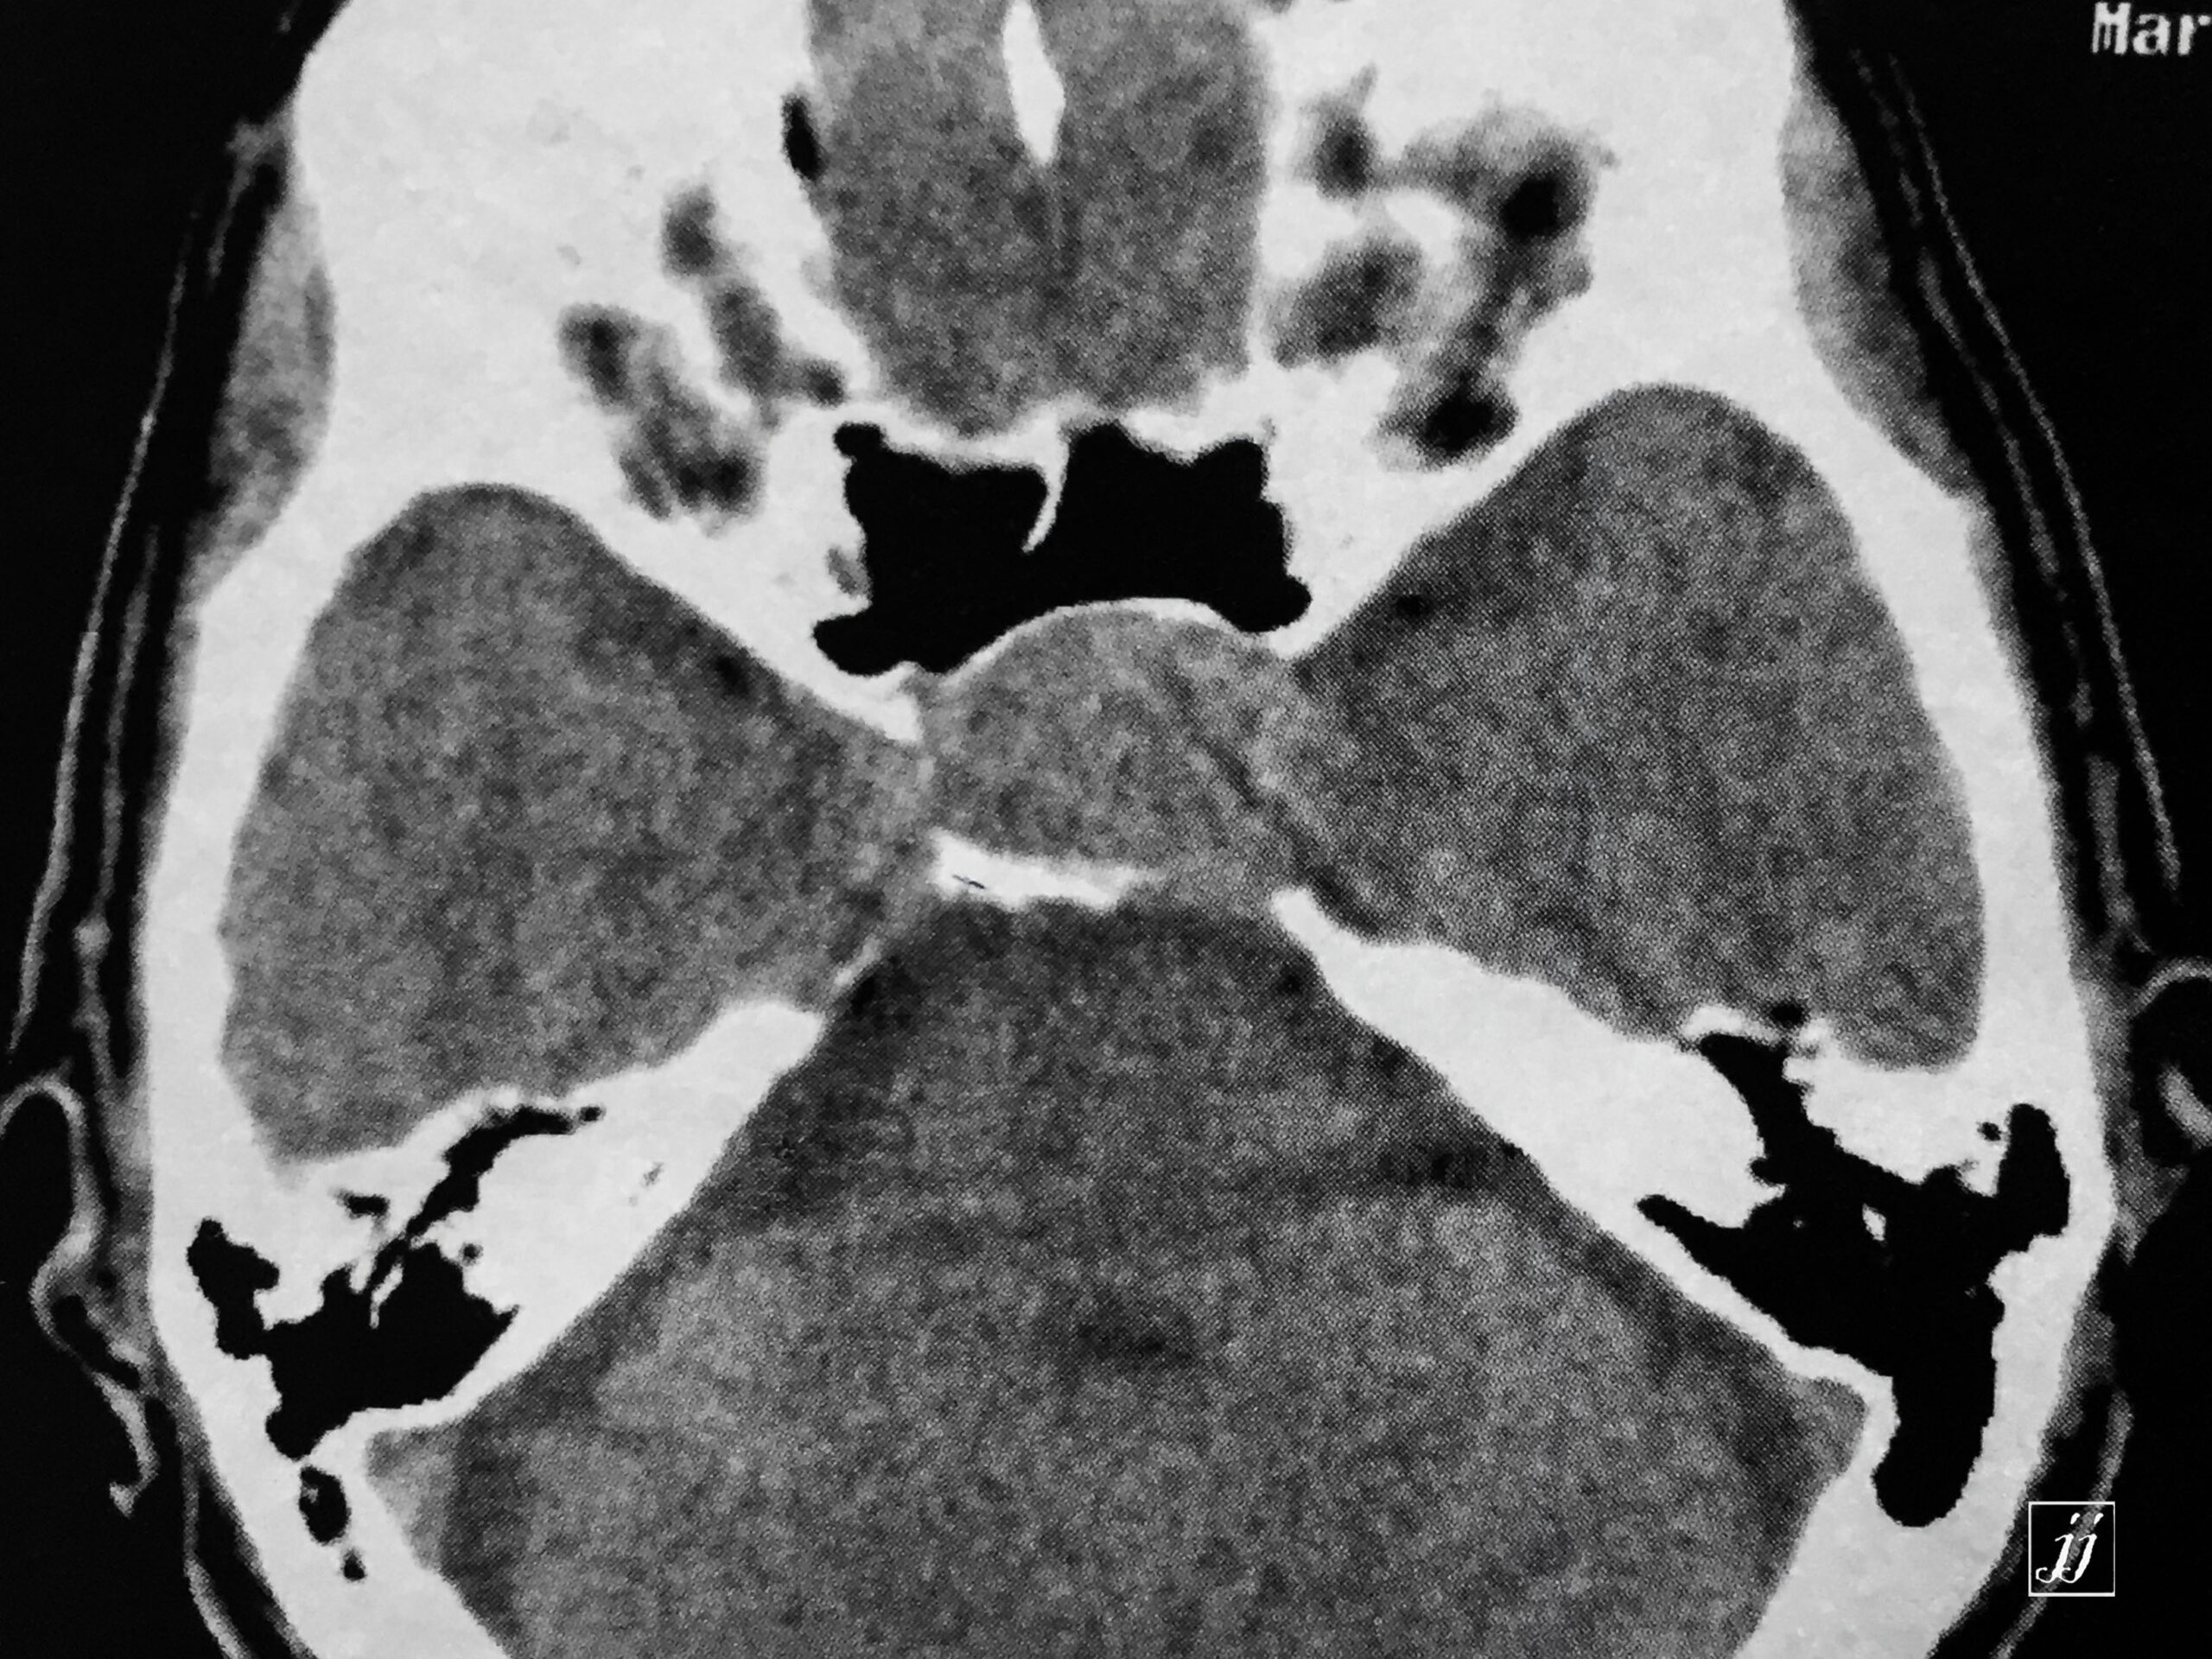

Brain- Hypophysis pituitary macro adenoma (1)